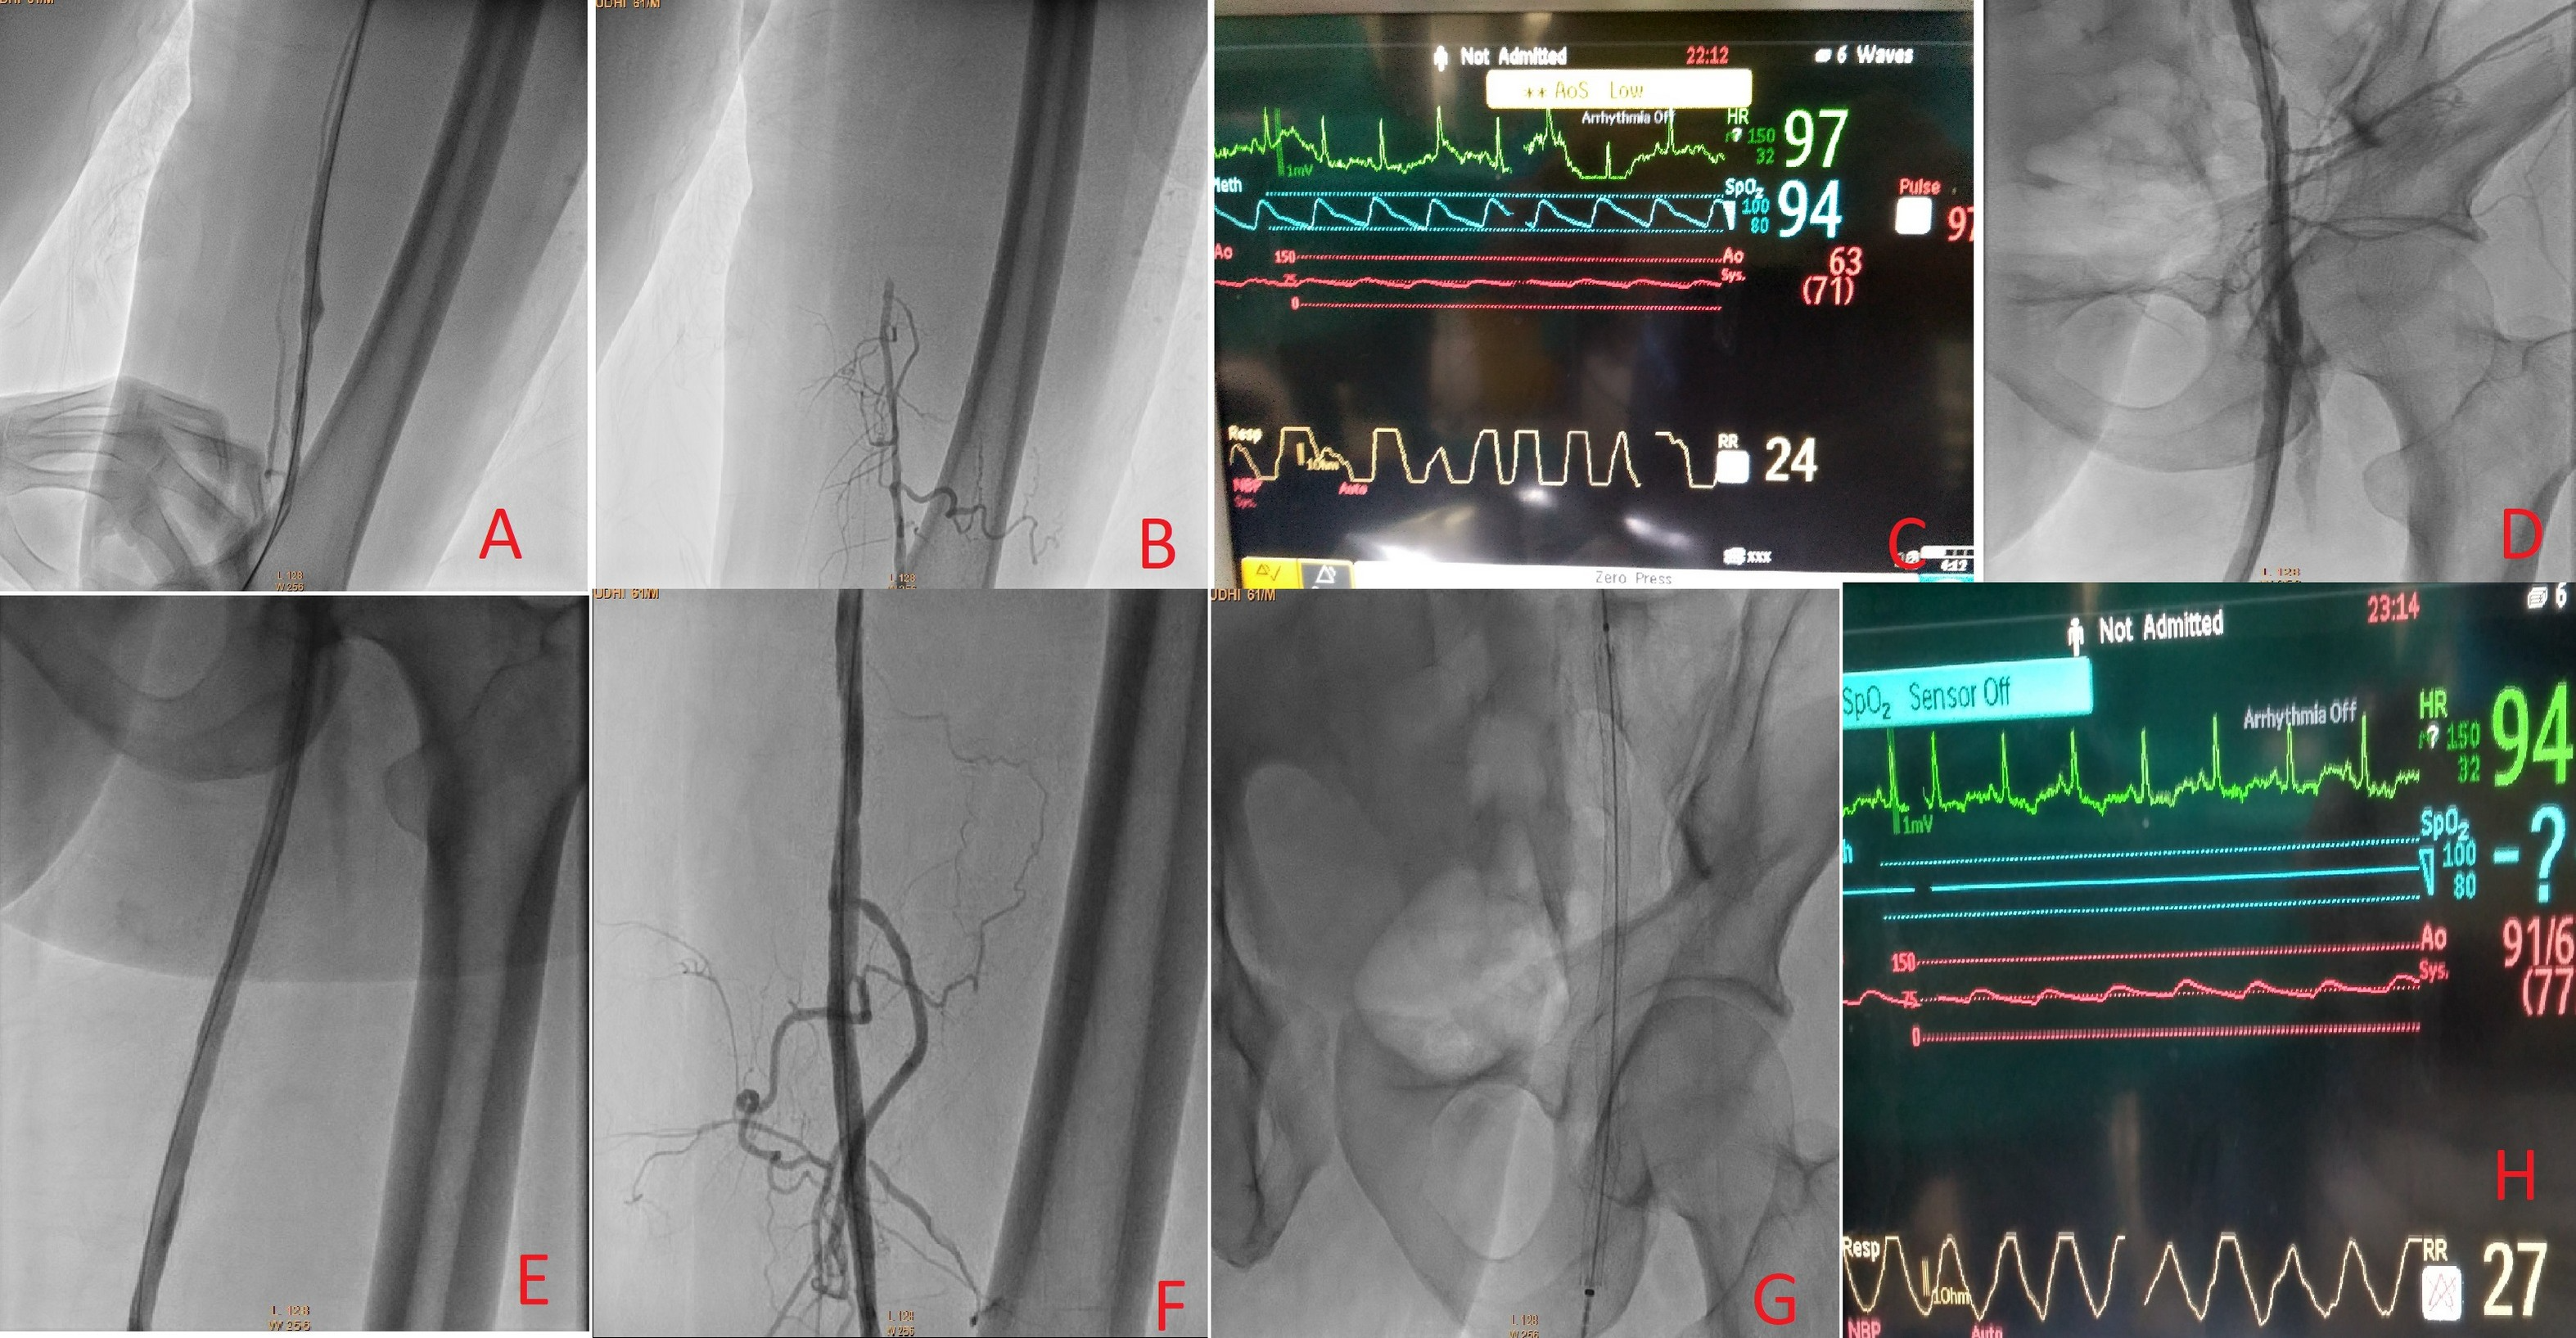

The entire length of the lesion was crossed retrogradely with the support of the Optitorque diagnostic catheter (Terumo) and exchange-length wire (Terumo). The patient’s abdominal aortic pressure was 148/84 mm Hg. The iliofemoral area was dilated with a 5 × 80 mm Armada balloon (Abbott Vascular). The distal SFA systolic pressure improved to 92 mm Hg because of flow limiting dissection in the iliofemoral area and mild dissection in the distal SFA area (Figure 2). The SFA was almost normal in its middle two-thirds. The ugly dissection in its proximal part was stented using a 7 × 80 mm self-expanding stent (Abbott Vascular) with a very good angiographic result.

However, the systolic pressure did not show significant improvement when the popliteal artery sheath pressure was checked. The blood flow via the side arm of the sheath was very slow. Thrombus was suspected, and we avoided flushing the sheath to prevent possible embolization of the thrombus. The popliteal sheath was exchanged using another 6 Fr sheath, and the removed sheath showed clots when flushed (Figure 3). The patient was given an additional dose of 5000 IU unfractionated heparin, and the popliteal sheath pressure became the same as the abdominal aortic pressure. We left mild distal dissection of the SFA to heal naturally, and there was no further claudication at the follow-up the next month. Triphasic flow was seen on a follow-up arterial Doppler test.